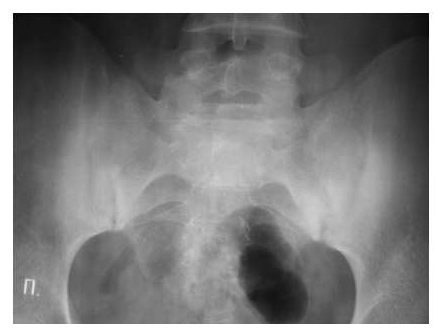

К примеру, при повторных атаках подагрического артрита клиническая симптоматика в виде боли и отечности может быть наиболее выражена в голеностопных суставах, а плюсне-фаланговые суставы могут оставаться интактными, и частой ошибкой является проведение больному рентгенографии голеностопных суставов, которая в данной ситуации малоинформативна. Аналогичная тактика и в ситуации с подозрением на реактивный спондилоартрит или периферическую форму анкилозирующего спондилоартрита с поражением голеностопных суставов. Патогномоничные рентгенологические изменения необходимо выявлять в крестцово-подвздошных сочленениях и позвоночном столбе, а рентгенологических изменений в периферических суставах, особенно в начальной стадии болезни, может не быть.

Нужно отметить, что в целом проведение рентгенографии голеностопных суставов из-за ее крайне низкой информативности нужно проводить редко и по строгим показаниям в случаях изолированного поражения одного голеностопного сустава и подозрении на специфическую (туберкулезную, гонококковую) природу артрита. Этот дефект влечет за собой необоснованную лучевую нагрузку и дополнительные материальные затраты для больного при проведении повторных необходимых для уточнения диагноза исследований.

Часто при псориазе рентгенологические проявления в мелких суставах кистей и стоп сочетаются с воспалительными изменениями крестцово-подвздошных сочленений сакроилиитами, обычно двусторонними асимметричными или односторонними.

Для серонегативных спондилоартритов более типичным является наличие эрозий суставных поверхностей в дистальных отделах стоп.

Рис. 7. Двусторонний сакроилиит у больного серонегативным спондилоартритом.

Околосуставной остеопороз в отличие от РА выявляется только в острую стадию артрита. Одна из основных локализаций, где развиваются костные пролиферации - это краевые отделы крестца и подвздошных костей (рис. 7).